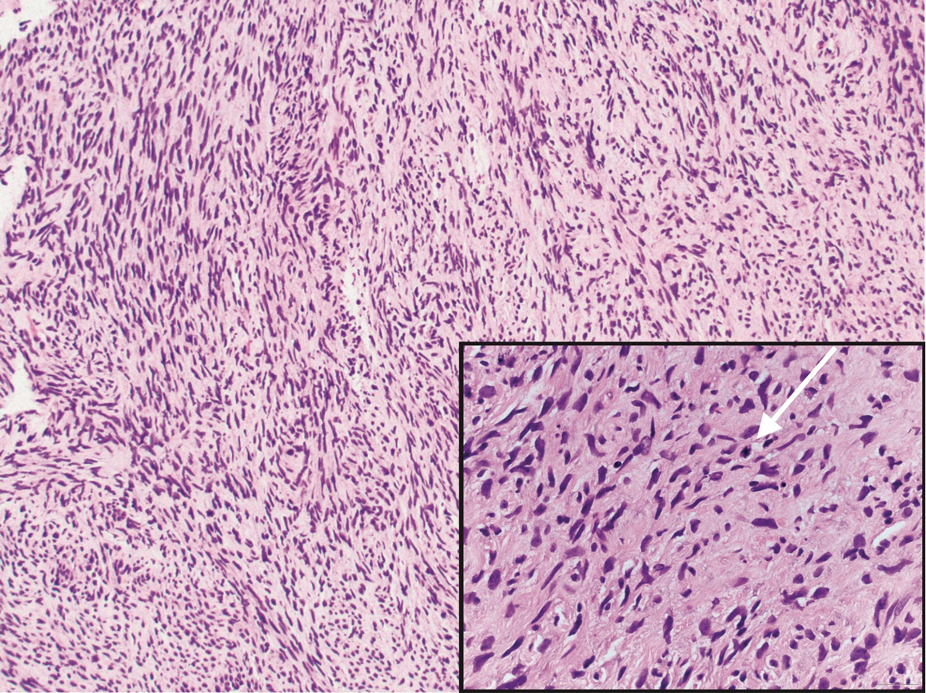

Malignant peripheral nerve sheath tumors are aggressive malignant spindle-cell tumors that may be associated with NF1 or occur sporadically.9,14 The spindle cells are arranged in fascicles, and these tumors can have areas of necrosis, hemorrhage, and high mitotic activity.9,15 The spindle cells may be arranged in a herringbone pattern, and alternating areas of hypocellularity and hypercellularity impart a marbled appearance (Figure 5).16 Malignant peripheral nerve sheath tumors frequently exhibit inactivation of the SWI/SNF-related, matrix- associated, actin-dependent regulator of chromatin subfamily B member 1 gene and loss of integrase interactor 1 protein. Transformation from plexiform neurofibroma to malignant peripheral nerve sheath tumor frequently is accompanied by progressive genomic changes.17 Malignant peripheral nerve sheath tumors differ substantially from PEN in their aggressive histologic features, including nuclear atypia and mitotic figures, which are absent in PEN.

FIGURE 5. Malignant peripheral nerve sheath tumor demonstrates fascicles and whorls of hyperchromatic spindle cells, with pleomorphic nuclei and mitotic activity (white arrow pointing to mitotic figure)(H&E, original magnification ×100 [inset, original magnification ×400]).